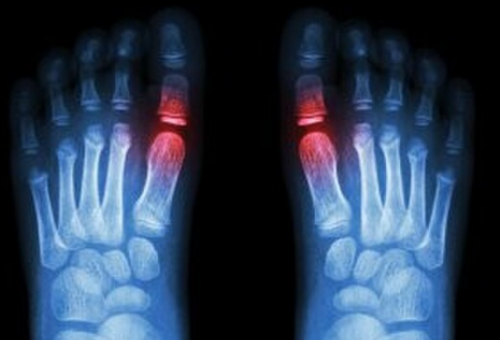

Sesamoiditis – ‘bottom of the big toe pain’

Sesamoid is a term that suggests a bone suspended in a joint capsule or tendon. The most obvious sesamoid in the body is the patella (or knee cap) which is suspended in the quadricep tendon. The sesamoids we are looking at in this article are under the base of the forefoot underneath the big toe joint. The big toe joint has two small sesamoid bones, one on the inside of the joint and one on the outside.

The muscles that bend (flex) the big toes joint pass underneath the big toes joint, crossing over the two sesamoid bones. The bump that is formed by the two sesamoid bones acts as a fulcrum point for these muscles, giving the muscles the necessary leverage to flex the big toe. Every time you push off against the toe the sesamoids are involved, and eventually they can become irritated, even fractured. Because the bones are actually within the tendons, sesamoiditis is really a kind of tendinitis – the tendons around the bones become inflamed as well. The sesamoid bones also act to protect the underlying soft tissues during walking and running.